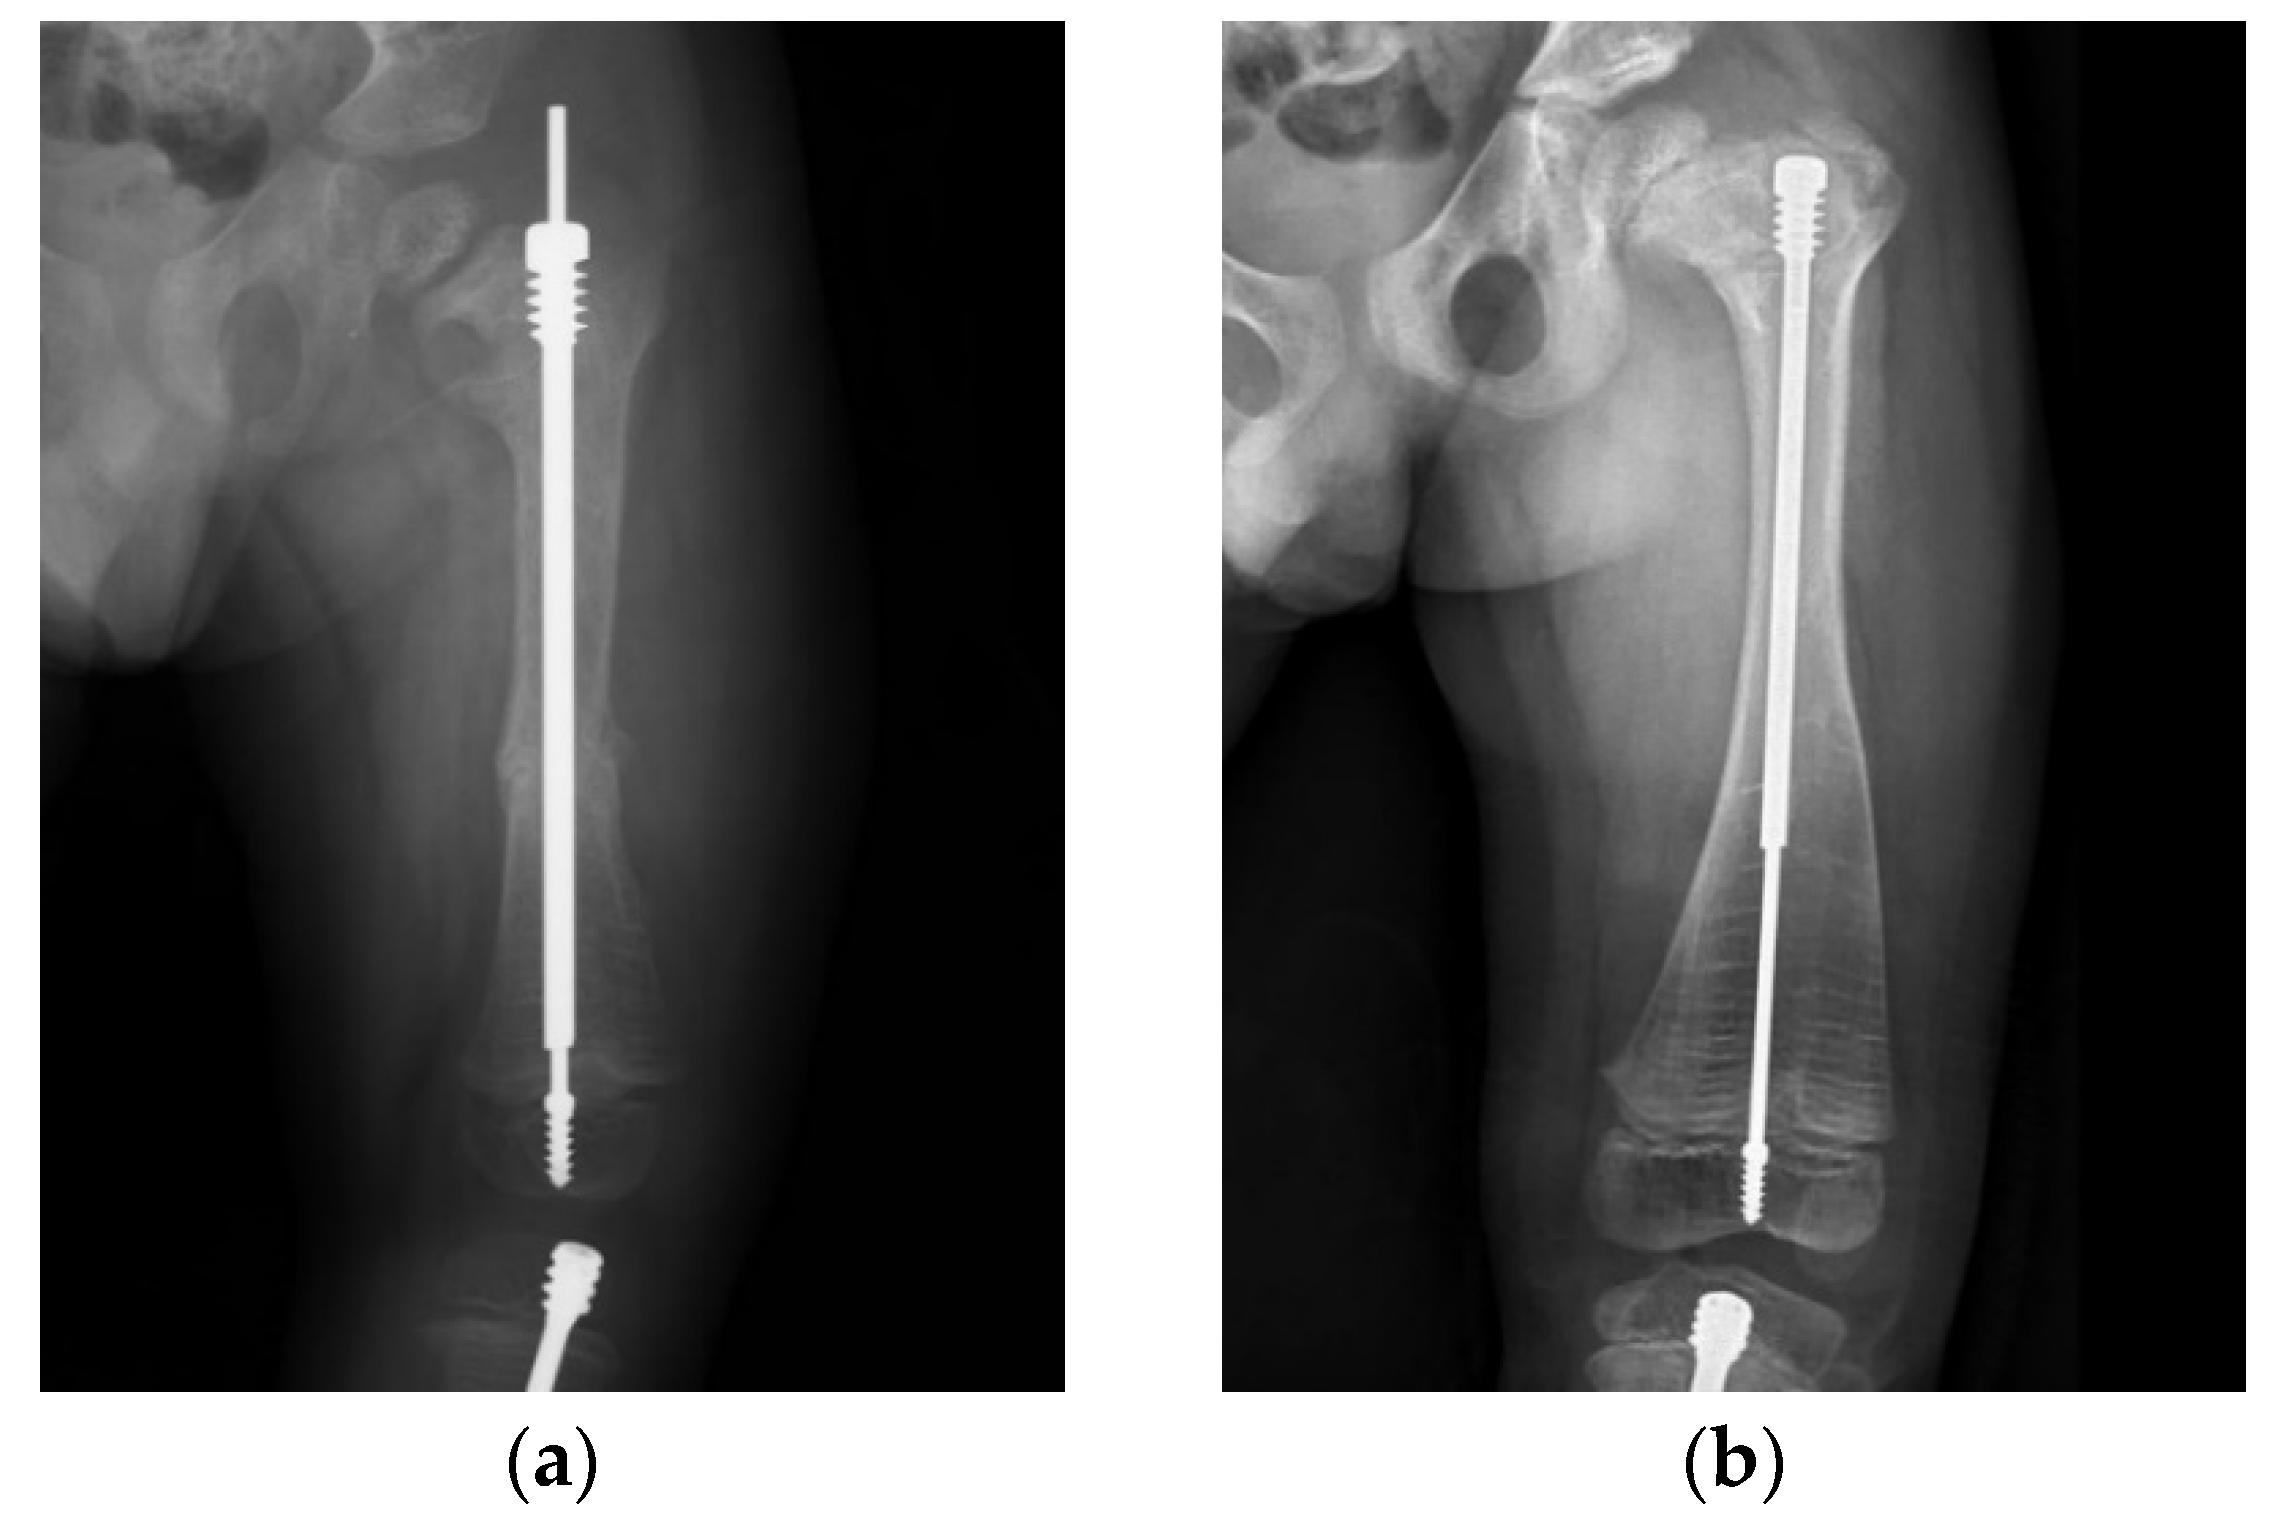

A 4-year-old male with type III OI presented as a classic model of insufficient depth of purchase and excessive bowing of the tibia (Figure 5). When axial force is applied to the limbs with excessive bowing, there will be an uneven force on the concave and convex sides, leading to delayed union (Figure 5a–c). Correction of the bowing with adequate osteotomy (or osteoclasis) before FD nail insertion is crucial (Figure 5d,e).

These principles may help to guide treatment and avoid complications. Six years after surgery, a male patient with type III OI (Figure 6) still maintained good nail telescoping without implant failure. We emphasize that sufficient depth of purchase is important to avoid migration of both the male and female components of the FD nail. A central nail position in the epiphysis ensures balanced alignment of the mechanical axis. Correcting excessive bowing cannot be over-emphasized. Following these principles, it is possible to avoid most implant-related complications during the long course of treatment for OI patients.

Figure 5. Lateral radiograph of the lower leg of a 4-year-old male post FD nail implantation. (a) There was insufficient depth of purchase into the epiphysis, and the position of the nail was anterior to the center of the epiphysis due to excessive bowing of the tibia. (b) As the patient grew, migration of the male implant (distal tibial nail pulled out of the epiphysis) was noted 2.5 years after implantation. (c) Excessive bowing resulted in uneven force applied to the concave and convex sides, which caused thickening of the cortex on the concave side and delayed union on the convex side. The aim of revision surgery was to correct bowing of the tibia with sufficient depth of purchase. (d) We corrected the bowing with adequate osteoclasis (arrow) before FD nail insertion. The position of the nail was at the center of the epiphysis in the lateral view after correcting for excessive bowing. (e) Good position of the FD nail and bone healing during regular follow-up.